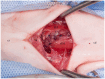

Results: Six cats underwent partial laryngectomy. The most common clinical signs in cats with laryngeal masses were stridor (n = 4) and dyspnoea (n = 4). In all cats, a full-thickness portion of one or several laryngeal cartilages was resected, including thyroid cartilage alone (n = 2), thyroid cartilage and arytenoid (n = 2), and arytenoid cartilage and epiglottis (n = 2). The resected laryngeal masses were reported to be lymphoma (n = 3), carcinoma (n = 1), laryngeal cyst (n = 1) and inflammatory laryngeal disease (n = 1). All cats survived the surgical intervention of partial laryngectomy. Four cats showed varying degrees of respiratory distress in the short-term postoperative period. A temporary tracheostomy tube was placed in two cats. No other postoperative complications were noted in the short- or long-term. Four cats were still alive at the time of writing. These cats survived at least 252 days.